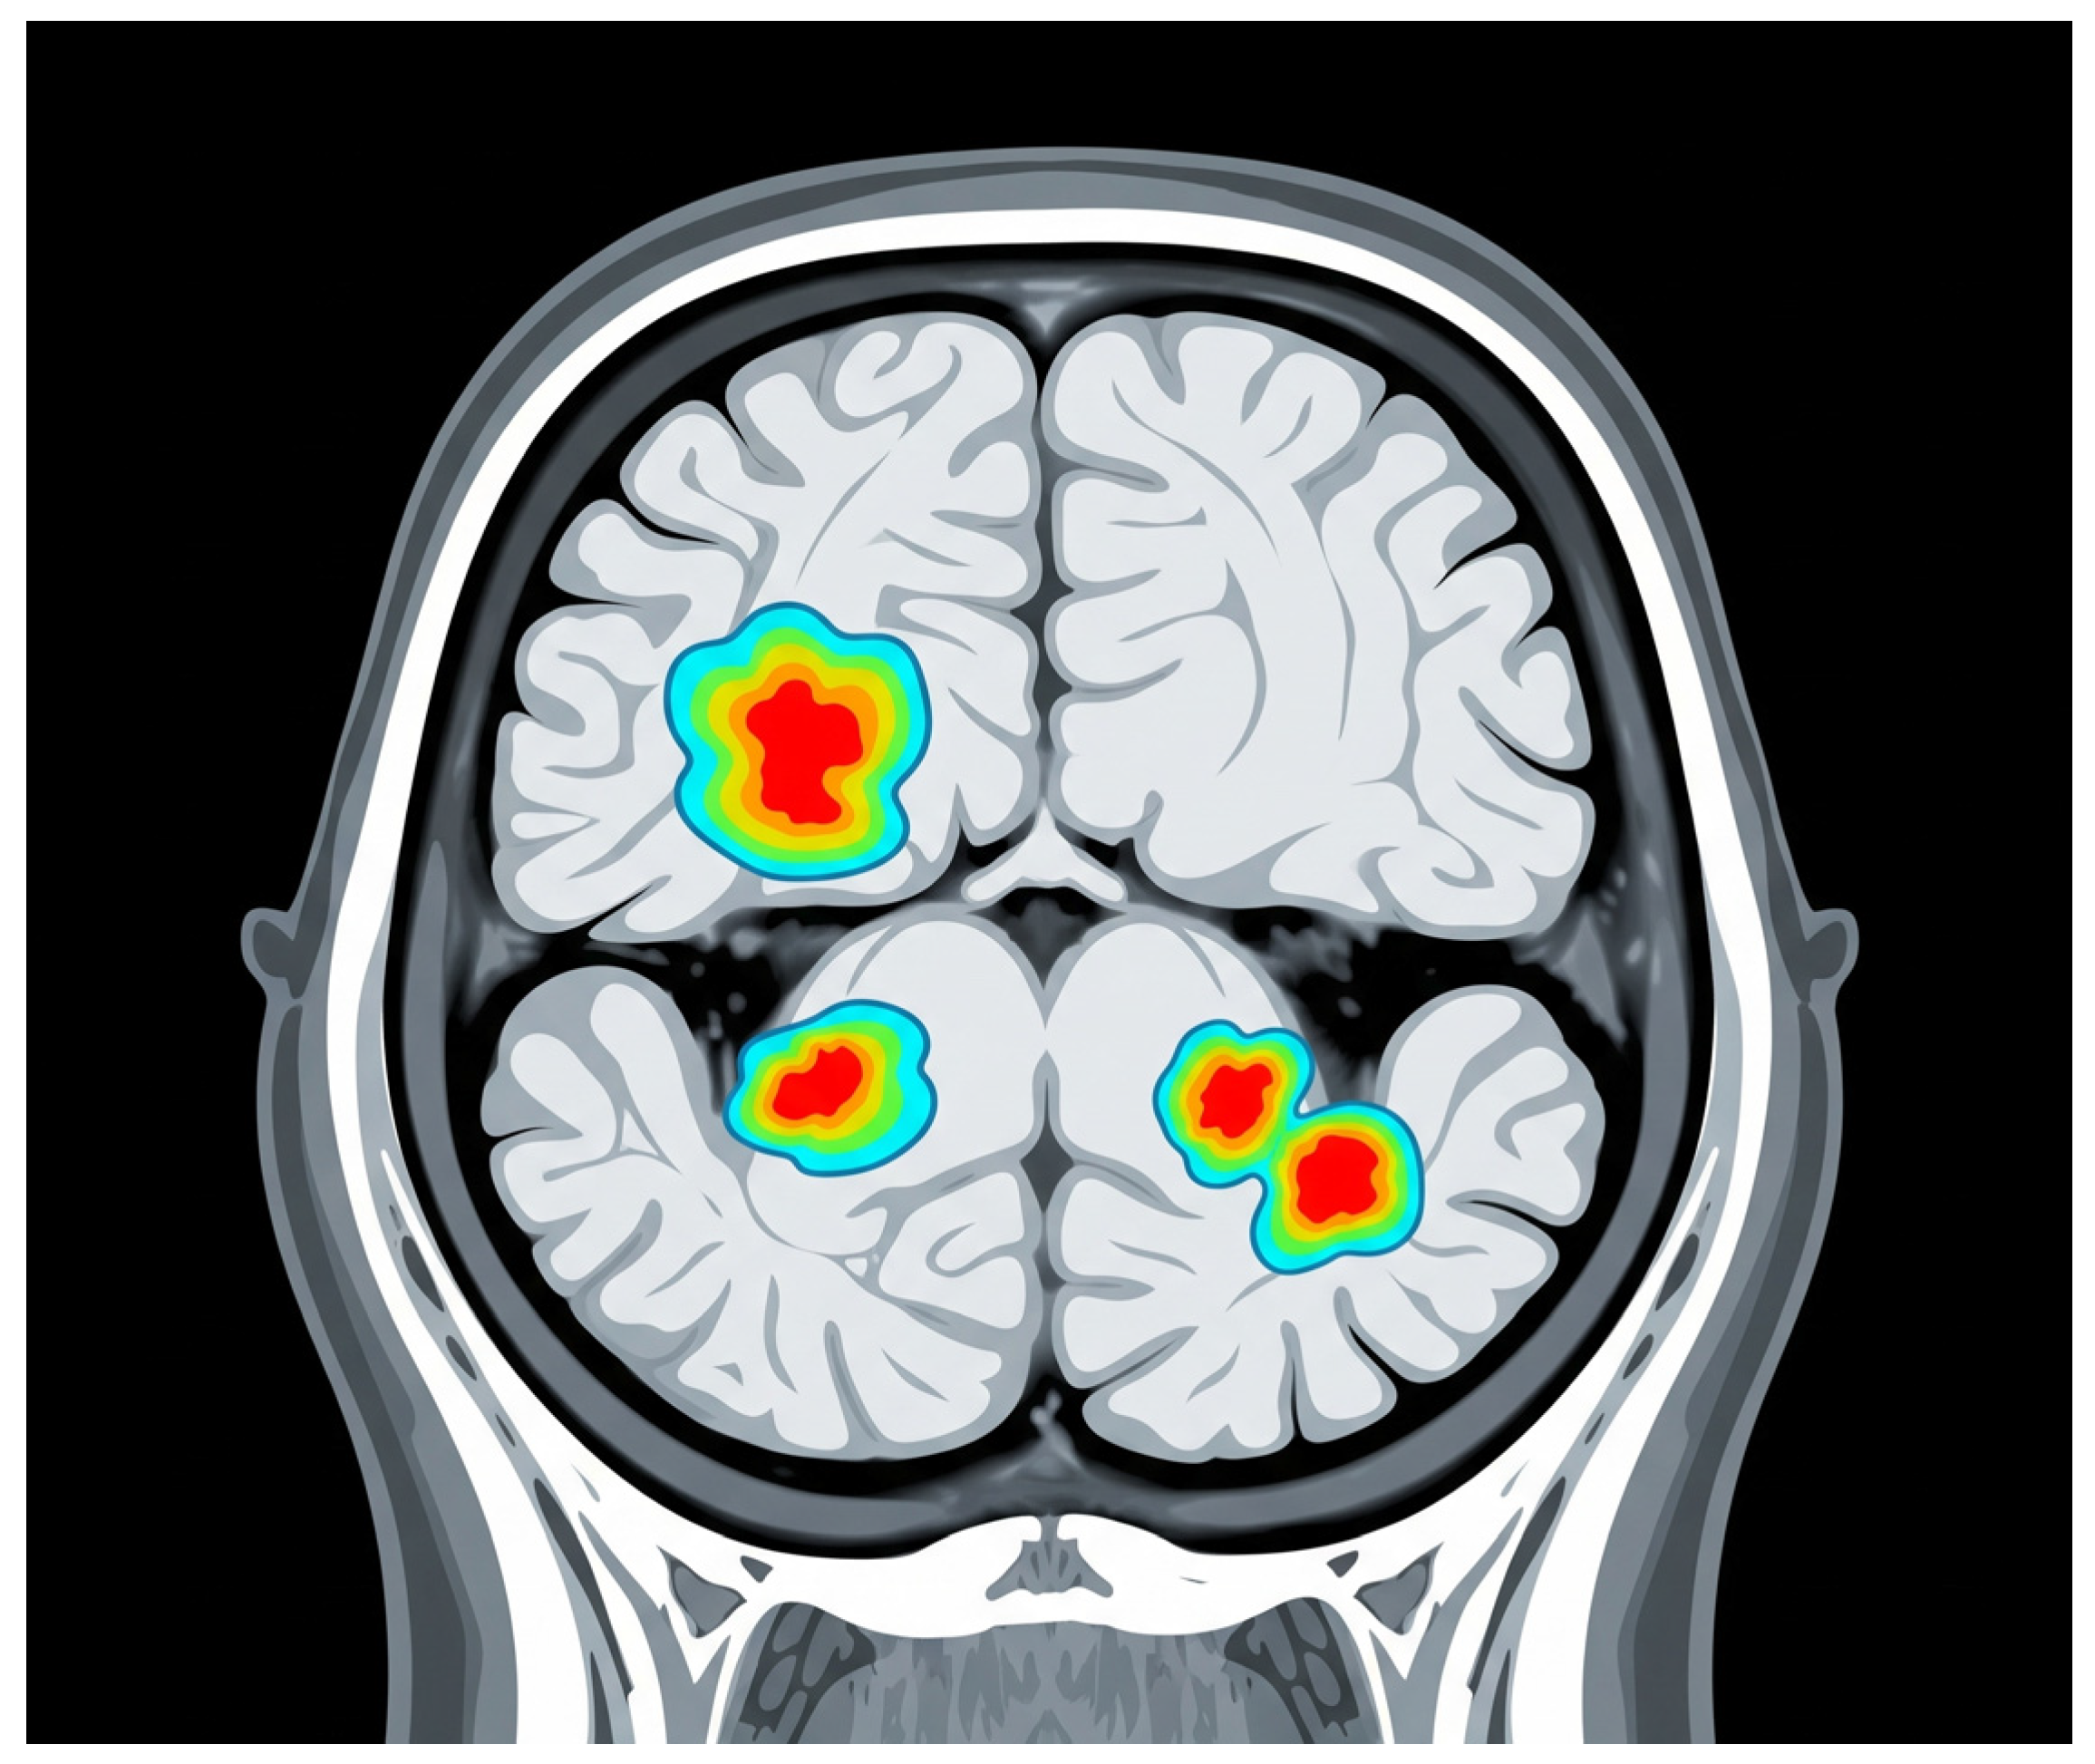

Advanced MRI techniques have enhanced the capacity to identify and characterize these lesions, providing valuable insights into their evolution and their relationship with clinical outcomes. The persistent and expanding nature of white matter lesions highlights their central role in SPMS pathophysiology and underscores the importance of longitudinal MRI studies for monitoring disease progression and therapeutic response, Figure 2 [38].

Figure 2. White matter lesions. The grey area represents the brain tissue, and the bright white areas represent the white matter lesions. These lesions are typically hyperintense (brighter) on T2-weighted MRI scans and represent areas of damage to the myelin sheath, which insulates nerve fibers in white matter. The red arrow indicates one of these distinct bright white lesions. In SPMS, these lesions indicate demyelination, axonal loss, and gliosis.

Jcm 14 04114 g002